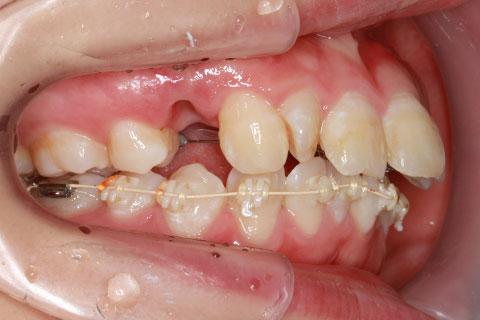

ハーフリンガル矯正3:上の歯のみ舌側矯正で治療(矯正期間24ヶ月)

治療前

治療中(開始直後)

治療中(開始半年後)

治療後

- 年齢・性別

- 25歳女性

- 治療期間

- 2年0ヶ月

- 抜歯

- 上下4番抜歯

- 治療費

- 110万円

- 治療内容

- 施術の副作用(リスク)

- 表側矯正と比較して、力学的な操作性が複雑なため、ボーイングエフェクトを起こしやすい。